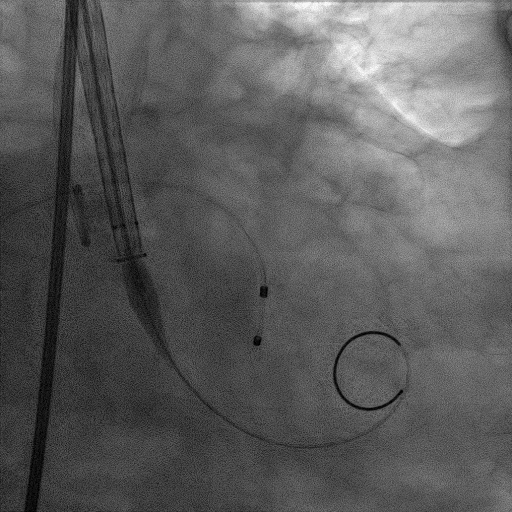

手术过程

患者麻醉方式为全麻,建立静脉通路后,穿刺右侧股静脉,预埋ProGlide缝合器,食道超声指导下房间隔穿刺成功,将Superstiff导丝送至左房,应用18F鞘管扩张穿刺部位,沿导丝将导引导管送入左房,MitraClip调整后顺利到达二尖瓣目标位置,在X线及食道超声辅助下,将Mitraclip NTR成形夹精确定位后,成功夹合二尖瓣A2-P2区,超声显示反流明显减少,多切面证实夹合组织充分,肺静脉多普勒波形由反向恢复正常,手术顺利结束,安返普通病房。

确定房间隔穿刺点:靠后

2D视图下测量大鞘长度2cm

3D视图打开夹子

X-plane:下第夹子尝试捕获2区

X-plane:测量前叶长25mm,后叶长14.2mm

X-plane:计算前叶捕获长度8mm,后叶捕获长度7mm

3D视图下观察二尖瓣双孔形态

3D-color:残余少量返流